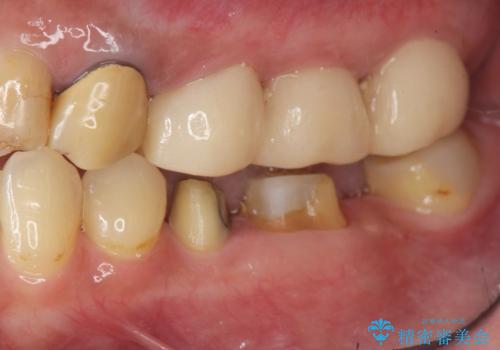

- 他院で根の治療まで終え、違和感が取れず相談に来院されました。

当該歯を精査したところ、歯根に破折が見られ抜歯を余儀なくされました。

抜歯後、インプラントを用いて咬合機能を回復すると共に周囲に強固な角化歯肉を移植することによりより長期にわたり安定したインプラント周囲環境となるよう治療を計画します。